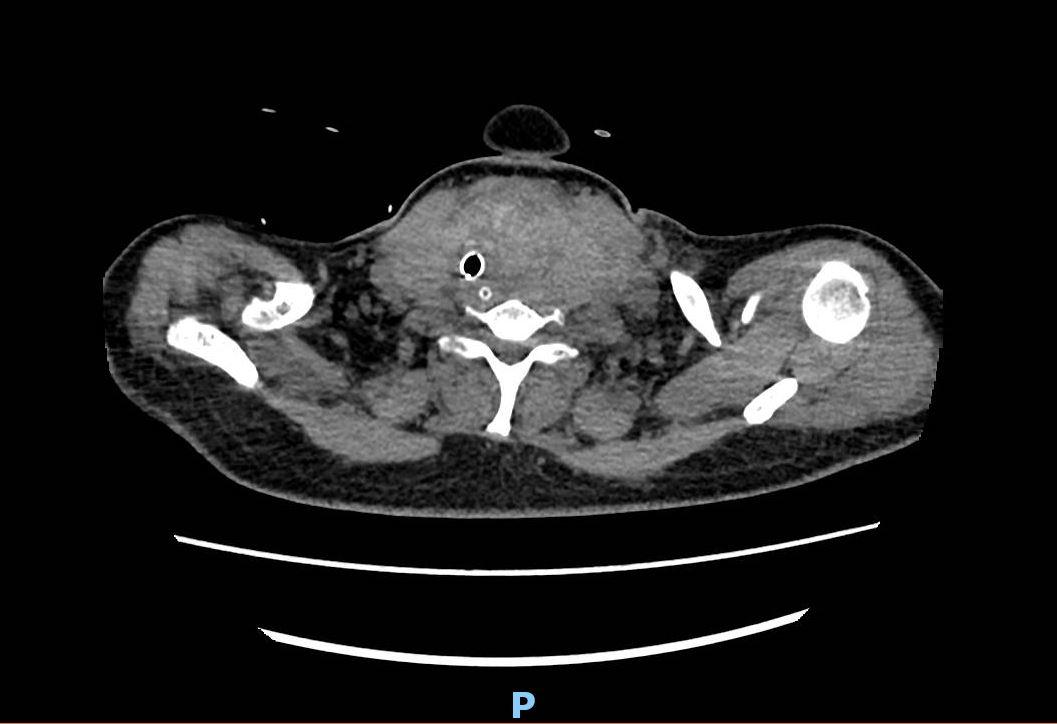

王女士的颈部巨大甲状腺结节存在多年,体积远超成人拳头,形似“大苹果”。她自认“良性无害”,没有重视。殊不知结节长期压迫已导致气管严重软化狭窄。近期,王女士持续咳嗽咳痰两周,剧烈的胸腔震动使本就脆弱的气道不堪重负,如同“压垮骆驼的最后一根稻草”,气道塌陷加重,加之肺炎分泌物堵塞,她突然出现呼吸困难伴意识模糊。

入院时,王女士仍依赖经口气管插管,生命体征不稳,颈部巨大肿物明显,肺炎及高血压增加围术期风险。甲状腺外科主任龙淼云团队评估后认为必须立即手术解除压迫根源。

ICU迅速响应,完成相应的术前检查与评估,手术即刻展开。术中探查发现肿物与颈总动脉、颈内静脉、迷走神经、喉返神经等重要结构致密粘连,长期压迫导致气管严重软化、塌陷,管腔显著狭窄,气管壁薄弱。手术操作空间受限,分离需极其精细、轻柔,以防损伤血管神经(如喉返神经损伤可致声嘶)及加重气管损伤。这对医生来说,就如同在豆腐上雕花。